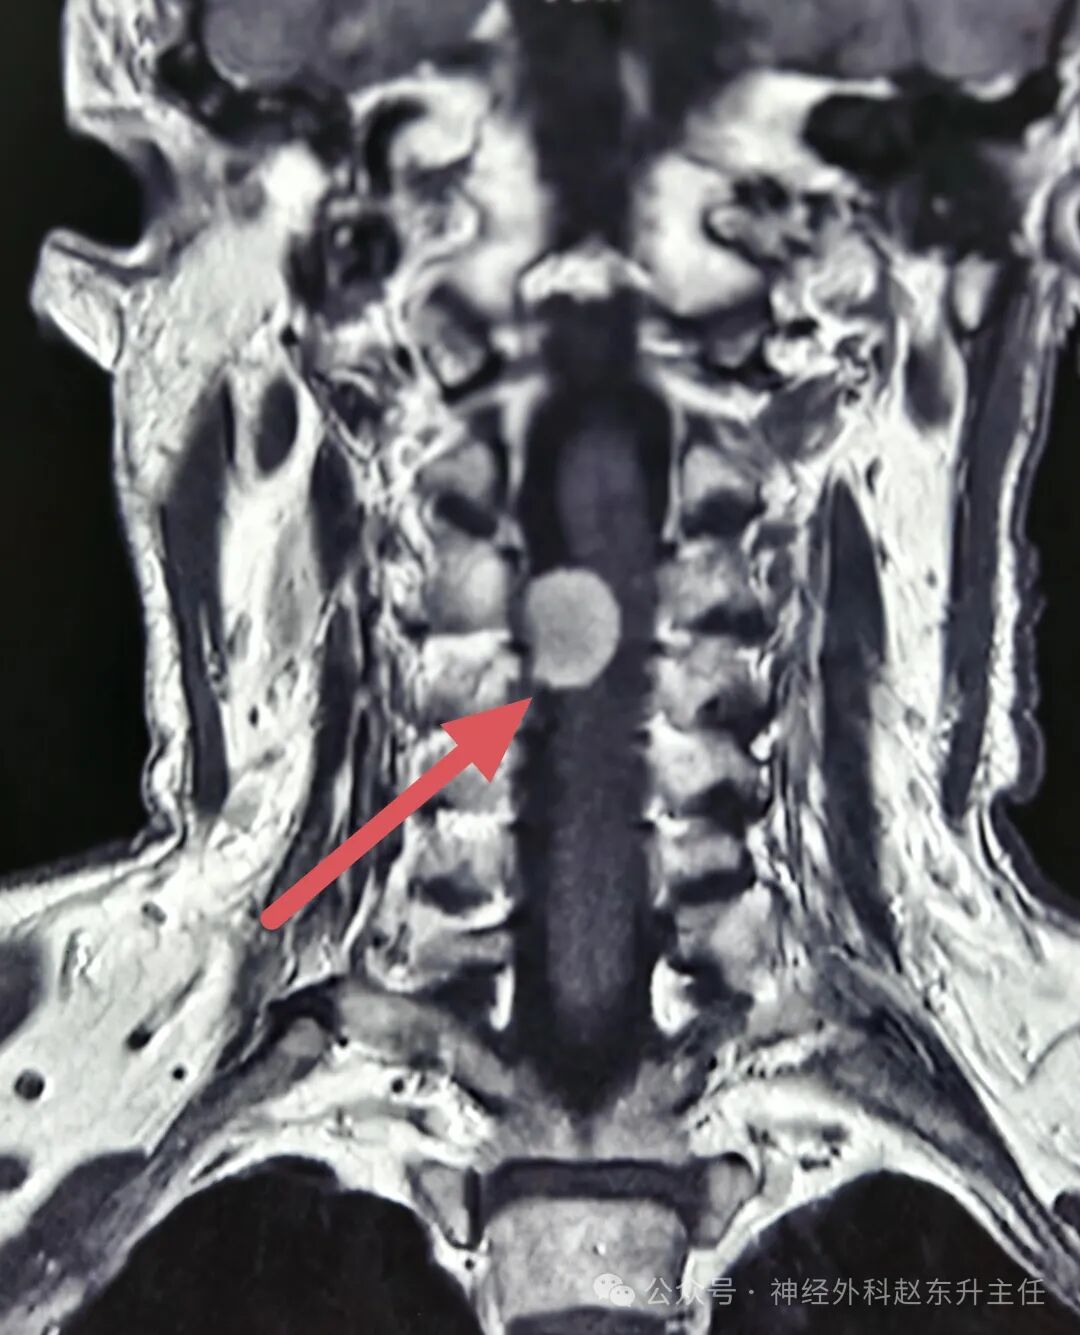

姚先生4月前感觉双手麻木,右手较明显,且持续加重,无颈肩部及上肢疼痛,在当地医院查颈椎MRI提示颈3-4椎管内肿瘤,肿瘤将近2cm大小,严重压迫脊髓。患者本身合并高血压,最高达170/105mmHg,看到这个结果,患者非常担心,随后找到西安市红会医院神经外科赵东升主任,赵主任看过片子后认为患者椎管内肿瘤为良性,手术可一次性治愈,建议手术治疗,家属在反复思想斗争下决定让赵主任主导手术。

IMG_20250530_155434.jpgIMG_20250530_155452.jpgIMG_20250530_155409.jpg术前磁共振增强显示肿瘤较大,质地较硬,压迫脊髓明显

手术在全麻下进行,使用高倍显微镜仔细剥离肿瘤,术中电生理监测,未损伤神经,并且将肿瘤完全切除。术后病理提示为神经鞘瘤。